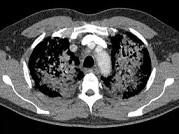

问题 男,51岁,呼吸困难,心悸,咳大量粉红色泡沫痰,结合CT,最可能的诊断是 ( )

选项 A.肺泡性肺水肿 B.间质性肺水肿 C.肺泡癌 D.肺泡蛋白沉积症 E.肺结核

答案 A